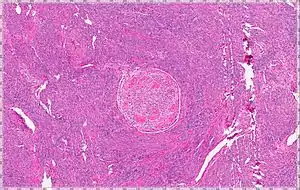

Intravenous leiomyomatosis is a rare condition seen exclusively in women in which leiomyomata, benign smooth muscle tumors, are found in veins. The masses are benign-appearing but can spread throughout the venous system leaving the uterus and even cause death when growing into the heart from the IVC.[1] While the possibility that these arose de novo from the smooth muscle in the blood vessel wall was considered, chromosomal analysis suggests a uterine origin.[2] Intravenous leiomyomata are usually but not always associated with uterine fibroids, and tend to recur.

a-c)Gross pathology- elongated, tan, rubbery mass 31×2.5×0.7 cm.